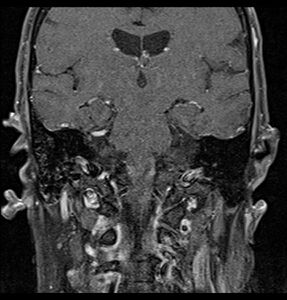

Primary treatment for this cancer, regardless of body site, is surgical removal with clean margins. This surgery can prove challenging in the head and neck region due to this tumor's tendency to show a perineural discontinuous growth, meaning that it follows nerves and different "nests" of the tumor can exist without a connection to the original tumor. Therefore, MRI-images should be analysed following nerve tracts up to the brainstem. Adjuvant or palliative radiotherapy is commonly given following surgery. For advanced major and minor salivary gland tumors that are inoperable, recurrent, or exhibit gross residual disease after surgery, fast neutron therapy is widely regarded as the most effective form of treatment.[13][14][15][16] Chemotherapy is used for metastatic disease. Chemotherapy is considered on a case-by-case basis, as data on the positive effects of chemotherapy are limited. Clinical studies are ongoing, however.[citation needed]

Coronal MRI showing right parotid adenoid cystic carcinoma with perineural spread of tumor along the facial nerve extending to the stylomastoid foramen